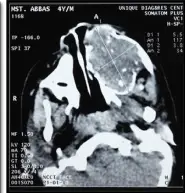

PATIENT UNDERWENT AN INCISIONAL BIOPSY FOR THE LESION IN 2010 WHICH SUGGESTED AMELOBLASTOMA. CBCT OF THE FACE WAS DONE IN 2010 AND IT GAVE THE IMPRESSION OF ODONTOGENIC CYST/AMELOBLASTOMA.

PATIENT THEN REPORTED TO OUR UNIT IN 2012. INCISIONAL BIOPSY REVEALED AMELOBLASTIC FIBROMA AND CBCT OF THE FACE WAS DONE WHICH GAVE AN IMPRESSION OF HEMANGIOMA / RHABDOMYOSARCOMA.

3D CT SCAN